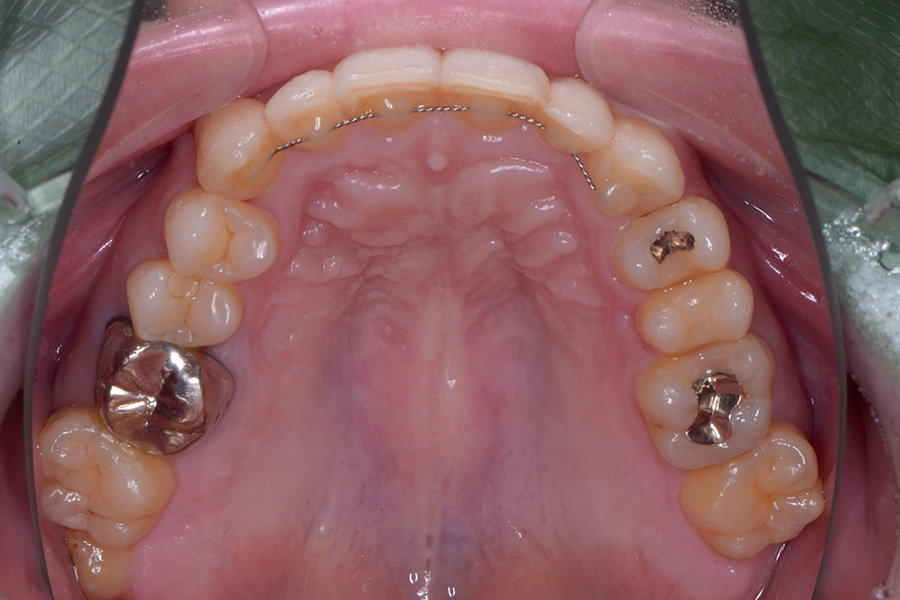

【30代男性】

八重歯を引っ込めたい

治療後

| 主訴 | 八重歯を引っ込めたい |

| 治療内容 | 上下顎ラビアル矯正(表側矯正) |